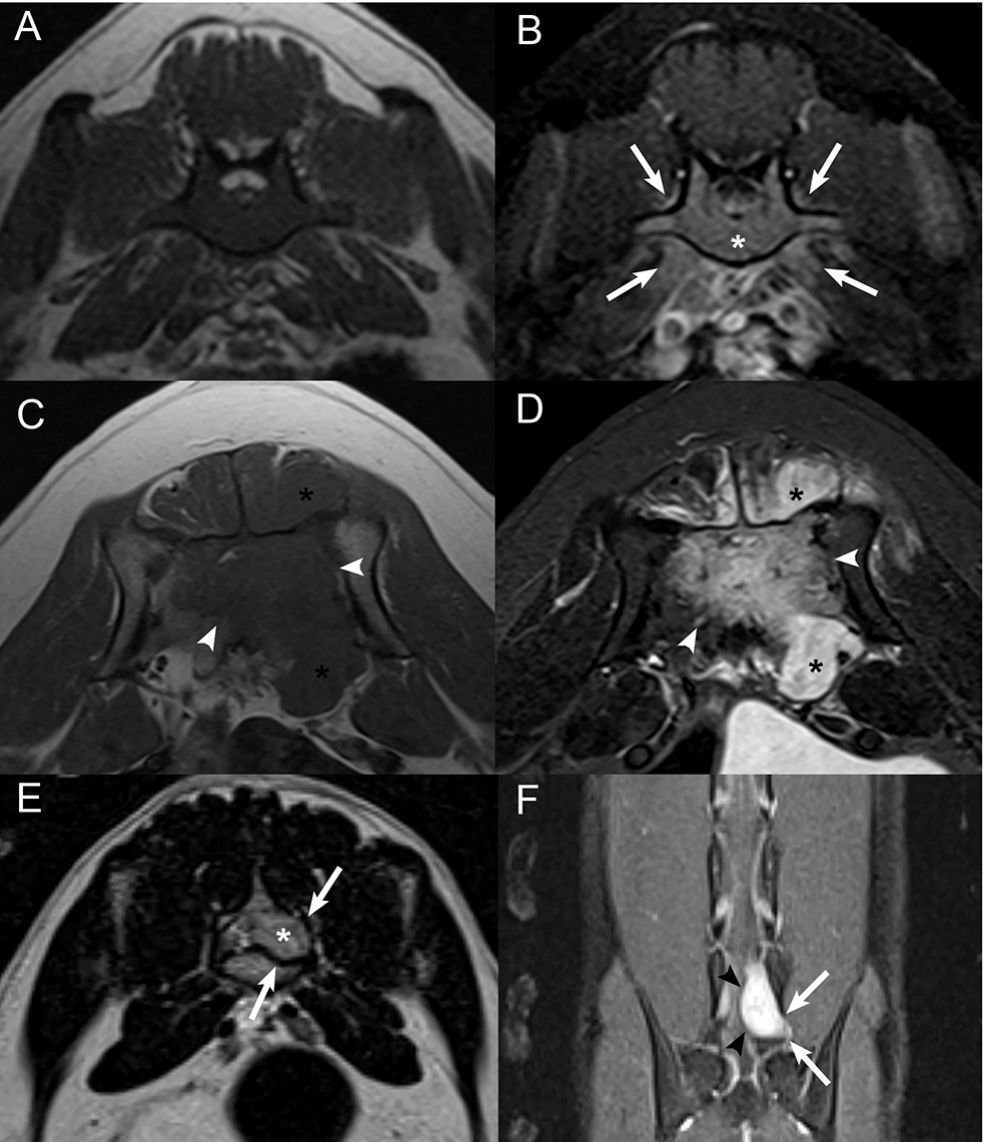

FIGURE 1 | Examples of cortical sparing, cortical lysis, and benign/reactive

bone change. Transverse (A) T1W image and (B) post-contrast T1W image

with fat saturation at the level of the seventh lumbar vertebra in an 8-years-old

male castrated Australian Cattle Dog diagnosed with lymphoma with cortical

sparing of the affected bone. There is homogeneous contrast enhancement of

the medullary cavity without cortical lysis (*) with mild contrast enhancement of

the adjacent paraspinal soft tissues (white arrows) and contrast-enhancing soft

tissue extending into the vertebral canal. Transverse (C) T1W image and (D)

post-contrast T1W image with fat saturation at the level of the sacrum in an

8-years-old male castrated Great Dane diagnosed with osteosarcoma with

extensive cortical lysis of the affected bone. There is a large, ill-defined,

heterogeneously contrast-enhancing mass centered on the sacrum (white

arrowheads) and extending into the vertebral canal and paraspinal soft tissues

(*). (E) Transverse T2W image and (F) dorsal post-contrast T1W image with fat

saturation at the level of the caudal aspect of L7 and L7-S1 intervertebral

foramen in a 4-years-old male castrated domestic shorthair cat diagnosed

with a peripheral nerve sheath tumor with benign/reactive changes of the

affected bone. There is a strongly contrast-enhancing (black arrowheads)

extradural mass following the L7 nerve root (*) causing smooth widening of the

left aspect of the vertebral canal and of the left L7-S1 intervertebral foramen

(white arrows).